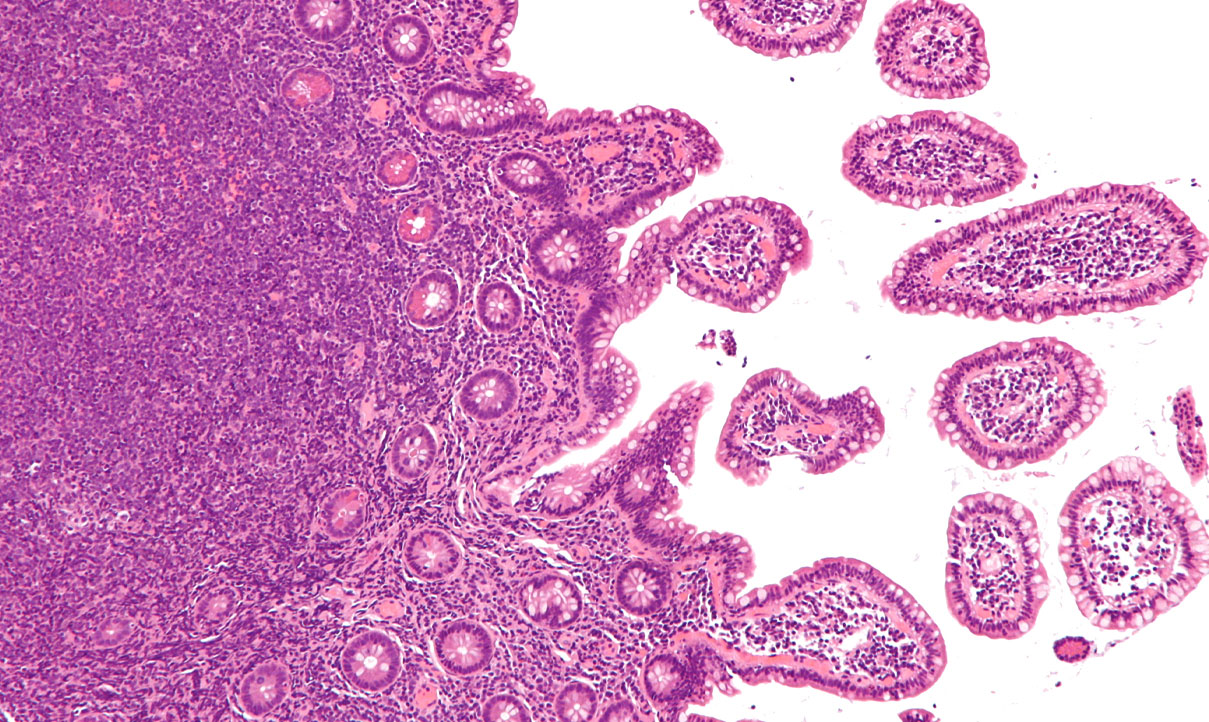

Αυτή η εικόνα δεν έχει ιδιότητα alt. Το όνομα του αρχείου είναι 4-22.jpg

Το μη-Hodgkin λέμφωμα δεν είναι μια ενιαία ασθένεια, αλλά μια ομάδα αρκετών καρκίνων. Ο Παγκόσμιος Οργανισμός Υγείας υπολογίζει ότι υπάρχουν τουλάχιστον 61 είδη NHL. Παρά το γεγονός ότι οι διάφοροι τύποι NHL έχουν μερικά κοινά χαρακτηριστικά, διαφέρουν ως προς την εμφάνισή τους κάτω από το μικροσκόπιο, τα μοριακά χαρακτηριστικά τους, την ανάπτυξή τους, τις επιπτώσεις τους στο σώμα και στην αντιμετώπισή τους.